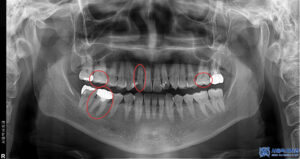

우선, 정밀 검사를 통해 기존에 진단받으셨던

충치 부위를 확인해 보았습니다.

그 결과, 양쪽 위 큰 어금니들은

치아와 치아 사이에 충치가 생겨있었고

오른쪽 앞니는 충치가 매우 심한 상태였습니다.

또한 오른쪽 아래 금으로 씌워진 치아는

씹을 때 마다 찌릿한 느낌이 든다고 하셨습니다.

결과적으로 양쪽 위 큰 어금니

2개는 인접면 우식으로 인해 인레이 치료가 필요했고

앞니는 신경치료 후 크라운 치료가

적합하다고 판단 되었으며,

오른쪽 아래 금니는 크라운 제거 후 재신경치료를

통해 치아를 살려보기로 하였습니다.